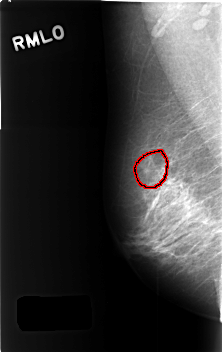

C_0448_1.RIGHT_MLO

RIGHT_MLO LINES 4568 PIXELS_PER_LINE 2880 BITS_PER_PIXEL 12 RESOLUTION 50 OVERLAY

FILE: C_0448_1.RIGHT_MLO.OVERLAY

TOTAL_ABNORMALITIES 1

ABNORMALITY 1

LESION_TYPE MASS SHAPE ARCHITECTURAL_DISTORTION MARGINS SPICULATED

ASSESSMENT 3

SUBTLETY 3

PATHOLOGY BENIGN_WITHOUT_CALLBACK

TOTAL_OUTLINES 1